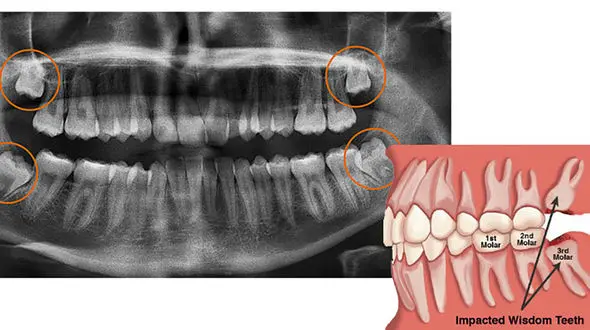

رکنا : دندان های عقل نهفته برای سلامت فرد خطرناک است.

سلامت رکنا : دندان عقل را باید به موقع کشید.

رکنا: دندان عقل چون سبب بهم ریختگی فرم دندان ها می شود بهتر است کشیده شود.